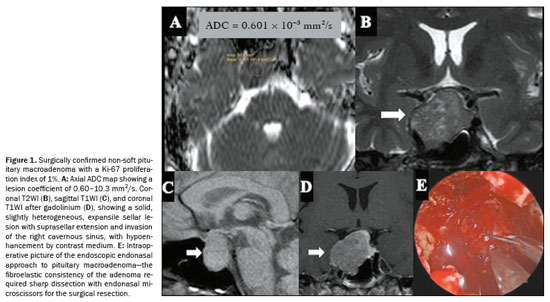

On DWI, a less frequently observed pattern of pituitary macroadenomas is one of lesions showing ADC values of 0.5–1.0 × 10−3 mm2/s. That ADC range has been linked to a higher probability that a tumor will have a non-soft consistency, as illustrated in the probability contour maps generated by the machine learning model. This imaging phenotype may indicate increased tissue cellularity or reduced extracellular space, features commonly associated with fibrous adenomas. However, the relationship between the ADC and tumor consistency appears to be nonlinear and may be influenced by other factors, such as tumor diameter, patient age, and patient sex. The heterogeneous nature of pituitary macroadenomas, including the coexistence of fibrotic and nonfibrotic areas (Figure 1), may account for the variability in ADC behavior, supporting the idea that ADC alone is inadequate to predict consistency with high reliability(21).

The consistency of a tumor, whether soft or non-soft, significantly influences surgical planning and requires skilled handling of various surgical tools. Soft tumors can often be removed easily using methods like aspiration or blunt curettage. However, approximately 10–15% of tumors are non-soft, posing significant technical challenges, with lower rates of complete resection and a higher risk of postoperative pituitary dysfunction

(22). In these situations, sharp instruments, curettage, ultrasonic aspirators, increased surgical access, or even craniotomy may be necessary